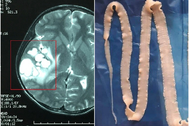

BS Lê Văn Thiệu, khoa Nhiễm khuẩn tổng hợp chia sẻ: "Kết quả chụp X-quang cho thấy có nhiều sán nằm ở các cơ. Bệnh nhân này có sở thích ăn những món tái, sống như: gỏi cá, rau sống và tiết canh. Trước đó, bệnh nhân đã có 3 đợt điều trị sán cơ và sán não".

Hình ảnh sán trong cơ của bệnh nhân (Ảnh: Bác sĩ cung cấp).